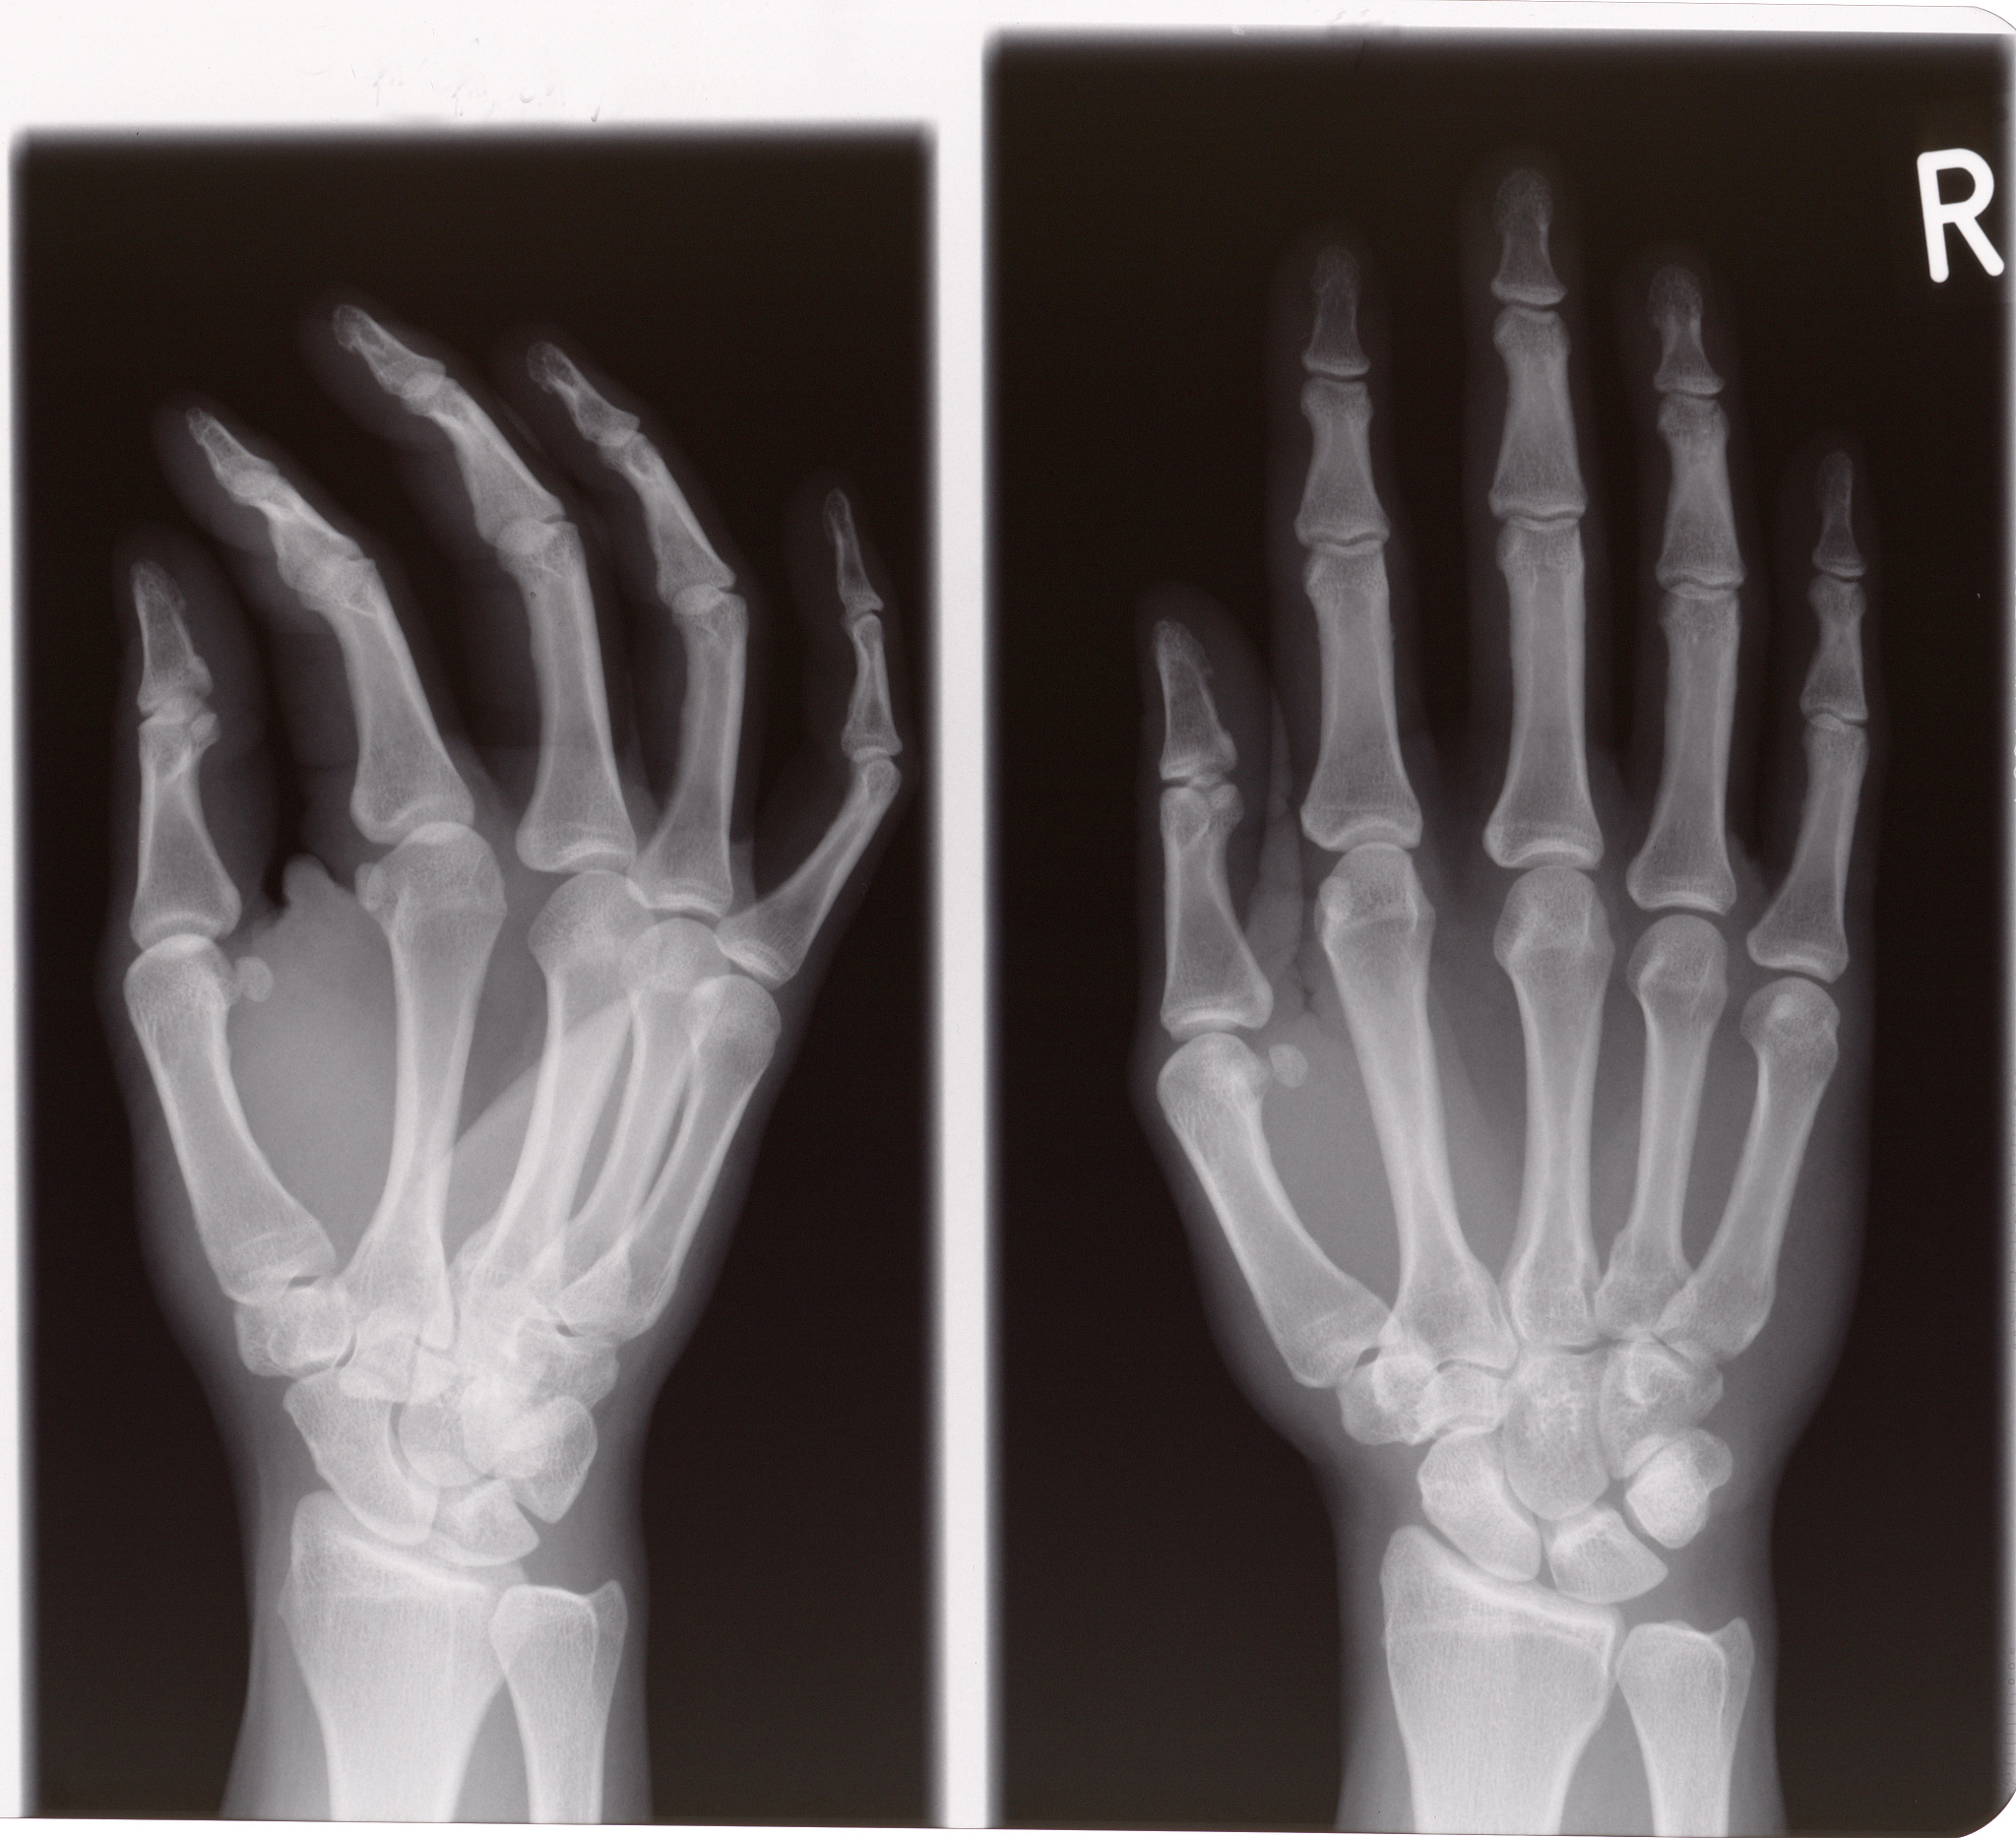

手部骨折是指手部骨骼的断裂或破裂。手部骨折可能涉及手腕、掌骨、指骨或指节的骨折。常见的手部骨折类型包括:

1. 腕骨骨折:包括桡骨和尺骨的骨折,造成手腕关节的疼痛和功能障碍。

2. 掌骨骨折:手掌骨折通常由于直接外力或手部的压力引起,常见于手掌中部。

3. 指骨骨折:手指骨折可能发生在掌骨或指节处,导致手指疼痛、肿胀和功能受限。

4. 指节骨折:指节骨折通常是由于手指受到外力冲击或扭曲造成的,可能导致手指关节的移位和疼痛。

手部骨折的症状包括疼痛、肿胀、淤血、活动受限和畸形。如果怀疑手部骨折,应尽快就医进行确诊和治疗。治疗手部骨折的方法包括保持稳定、使用石膏固定、穿戴矫形器或进行手术修复。康复过程中可能需要进行物理治疗和康复锻炼,以恢复手部功能和力量。